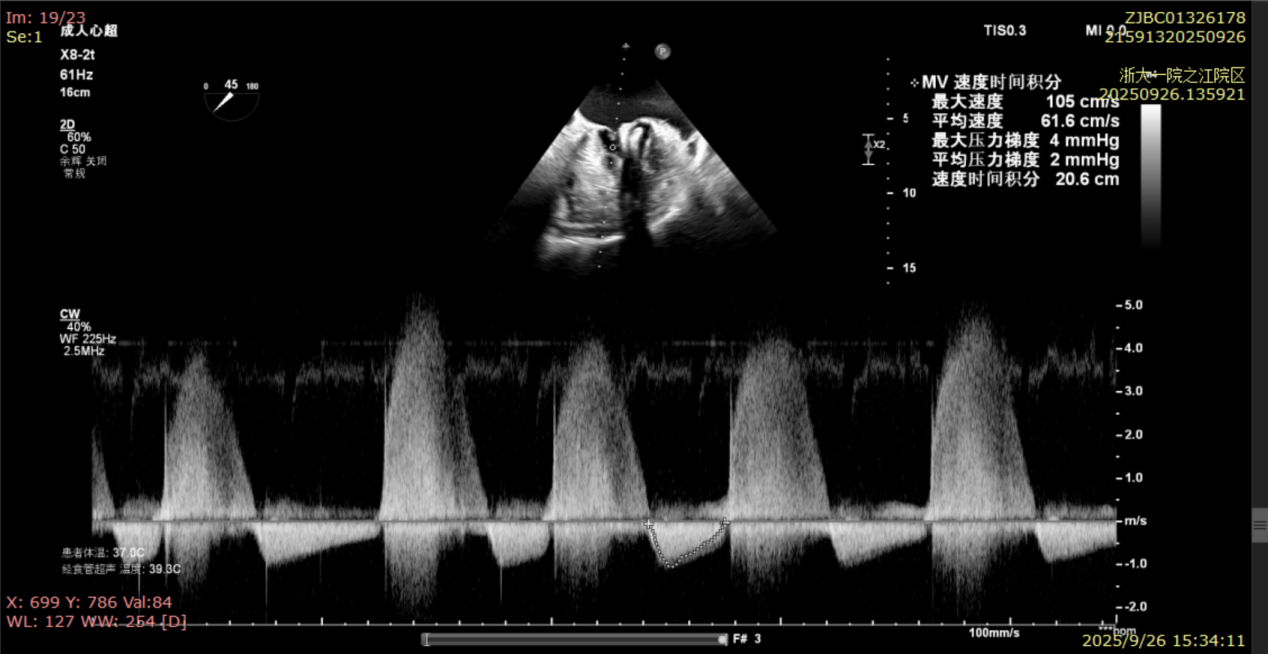

术前经食道超声显示:二尖瓣C1、P1区脱垂,重度关闭不全,彩色多普勒提示大量二尖瓣反流。术前瓣口面积MVA约5cm²,瓣环前后径AP约36.9mm,前叶A1约26mm,后叶P1约15.2mm。

术后即刻反流降为少量,剩余瓣口面积2.57cm²,平均跨瓣压差2mmHg。

术后复查超声心动图显示:二尖瓣轻度返流,三尖瓣中度返流,二尖瓣可见金属夹回声,启闭正常;各心室大小正常,升主动脉不宽,主瓣回声增强,启闭良好;二尖瓣舒张期峰值流速1.4 m/s,功能面积2.1 cm²,跨瓣平均压差约4 mmHg。